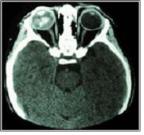

방사선 검사를 통해 종양의 외부 전이나 안구 내 위치 등을 보다 정확하게 알 수 있습니다.

[ 안종양 방사선 사진 ]